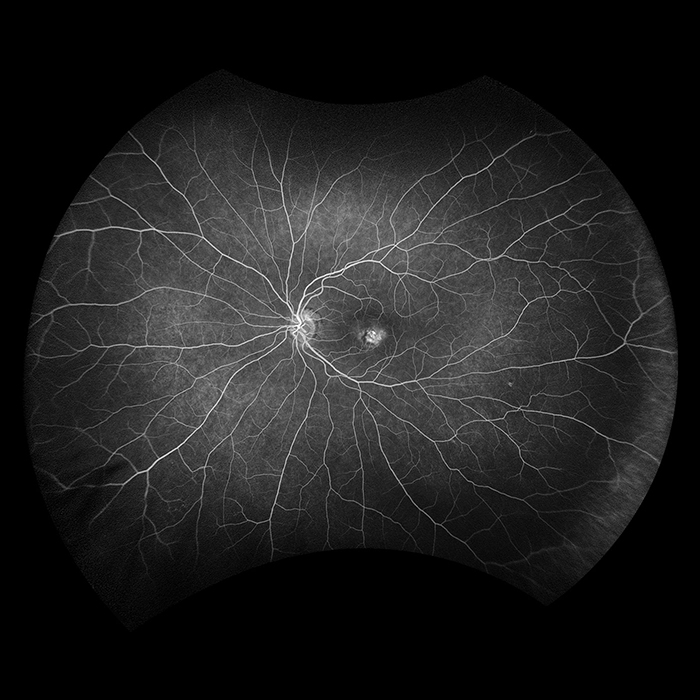

California

Unser beliebtestes Produkt, California, wurde für die medizinische Bildgebung entwickelt und ist ein Standard für Netzhautscreening-Programme. California ist in verschiedenen Bildgebungsmodalitäten erhältlich. California erzeugt in weniger als ½ Sekunde ein 200°-Bild der Netzhaut mit nur einer einzigen Aufnahme von unübertroffener Klarheit und beeinflusst das Management von Krankheiten wie DR, AMD, Geografische Atrophie, und Uveitis

Bildmodi und Ansichtsoptionen von California:

optomap Bildmodi

- Farbe rg

- Farbe rgb (verfügbar im kombinierten Modell rg/af/fa)

- Sensorisch Rotfrei

- Choroidal

- Autofluoreszenz

- Fluoreszenzangiographie

- Indocyaningrün-Angiographie